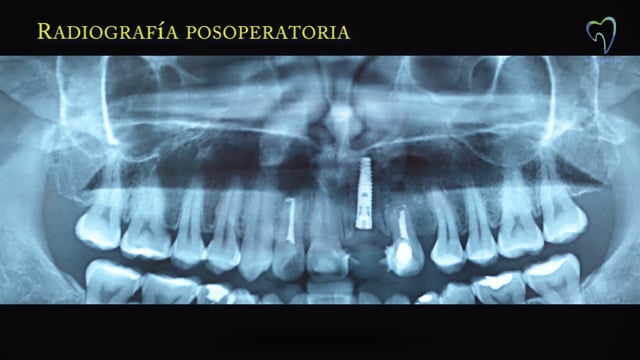

El fracaso endodóntico y el fracaso de una apicectomía terminó con la extracción de un incisivo central superior. La extracción se complementó con una regeneración ósea guiada. El video muestra la colocación del implante con la técnica flapless sin colgajo.